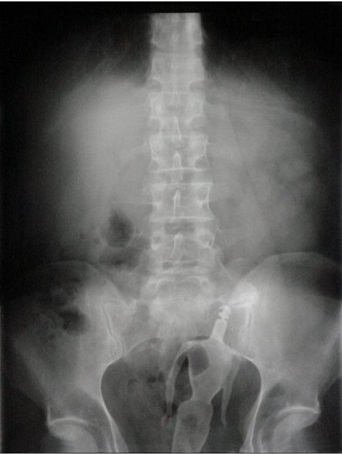

มาดูภาพเอกซเรย์ สารพัดสิ่งของที่เคยหลุดเข้าทวารหนัก

เผยภาพเอกซเรย์สุดอึ้ง สารพัดสิ่งที่เคยหลุดเข้าไปภายในทวารหนักผู้ป่วยทั่วโลก แปลกพิสดารกันจริง ๆ

การยัดสิ่งของต่าง ๆ เข้าไปในทวารหนักนั้น ไม่ว่าจะด้วยเหตุผลเพื่อหลบซ่อนการตรวจของเจ้าหน้าที่ทางการ หรือเป็นความผิดพลาดจากการแก้ขัดเมื่อเกิดอารมณ์ทางเพศก็ตาม สิ่งของที่หลุดเข้าไปนั้นล้วนแล้วแต่สร้างอันตรายให้กับอวัยวะภายในของผู้ป่วยได้หมด แต่ถึงจะเป็นอย่างนั้น เคสทางการแพทย์ว่าด้วยเรื่องของสิ่งแปลกปลอมที่หลุดเข้าไปในทวารหนักก็ยังมีให้เห็นอยู่เรื่อย ๆ ถมเถ แต่ละอย่างทำเอาอึ้ง ทึ่ง แบบไม่คิดว่ามันจะหลุดเข้าไปในทวารหนักได้จริง ๆ ดังเช่นตัวอย่างเคสที่เรานำมาฝากกันในวันนี้..